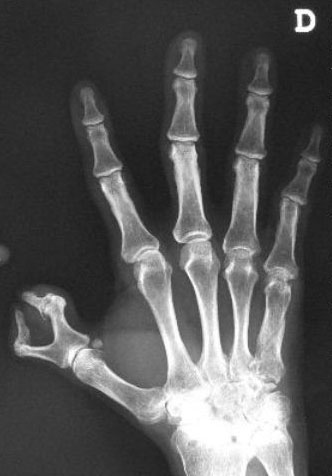

Carpo normal